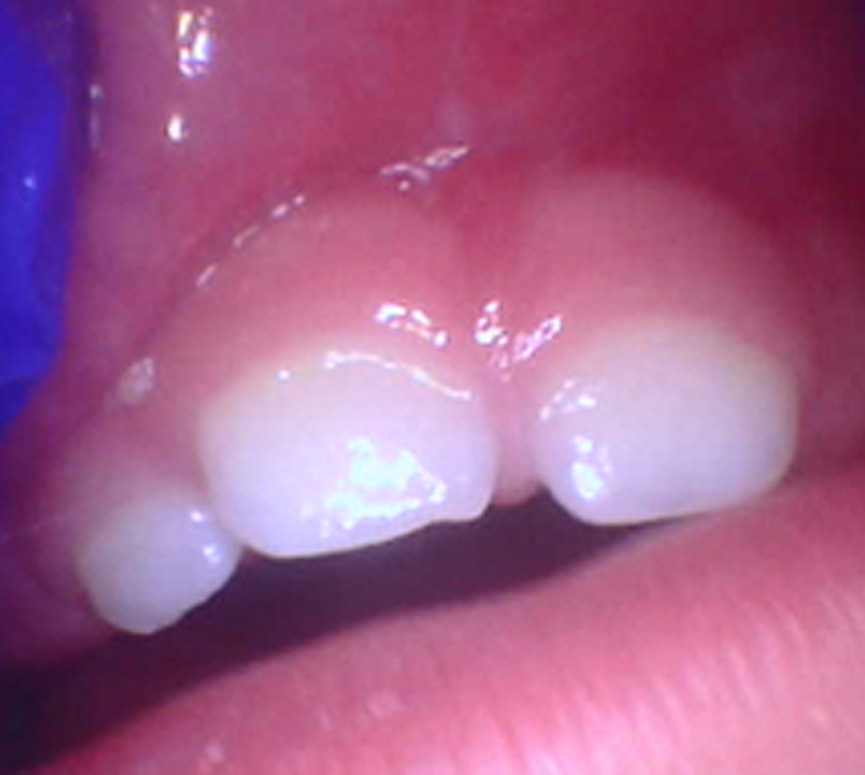

Frenectomy: Before and After

• Tongue Tie

An overly tight lingual frenum limits the tongue’s ability to lift, extend, or move freely—affecting feeding, swallowing, speech sounds, and oral mobility.